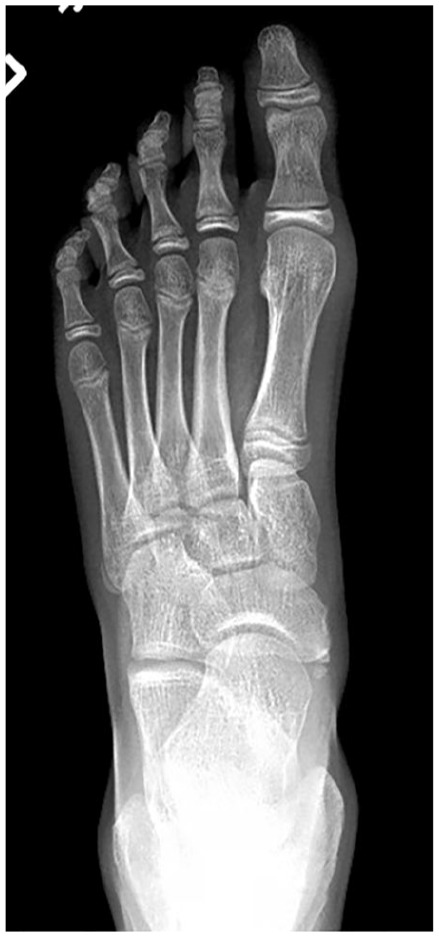

Background: An accessory navicular is a supernumerary ossicle located medial to the navicular bone, typically within the substance or insertion of the posterior tibial tendon, and can be a source of pain and dysfunction in active individuals.

Abstract Image